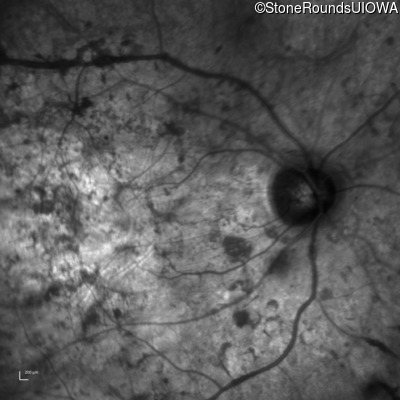

Infrared Fundus Photograph - Right - Hand Motion @ face sc

Exemplar